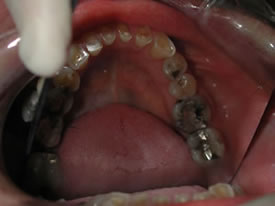

| Here's a close-up look at her upper arch (top

teeth) and lower arch (bottom teeth): |

After